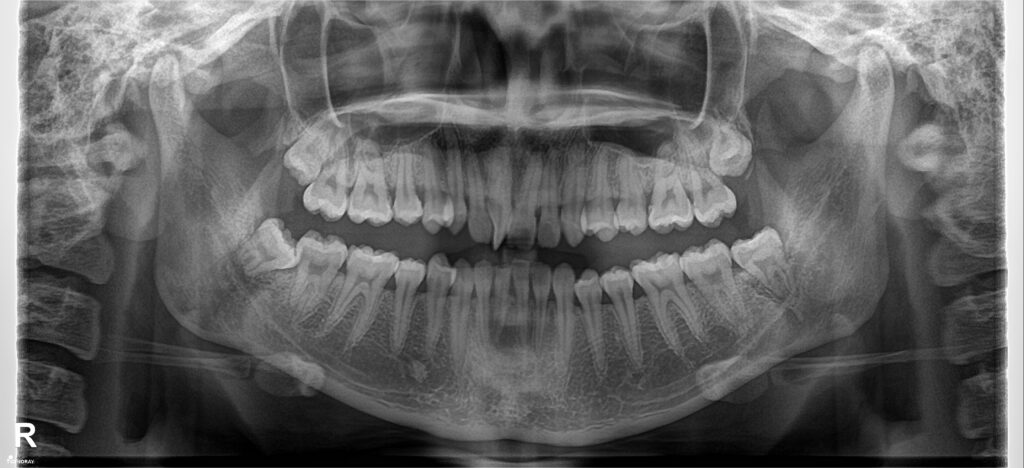

Một case sai khớp cắn hạng III góc đóng, với chen chúc cắn kéo nhiều răng. Giai đoạn san bằng và sắp đều đã được hoàn thiện trước đó. Dr Răng Hàm Nhỏ tiếp nhận và bẻ MEAW trên dây TMA 17×25 kết hợp thun 1/4 hạng III ngắn 6.5Oz trong 6 tháng. Giải quyết được hở khớp vùng răng hàm, lồng khớp hai hàm về tối ưu. Tinh chỉnh khớp cắn, duy trì và tháo niềng.

Kết quả so sánh phim chụp trước và sau điều trị.